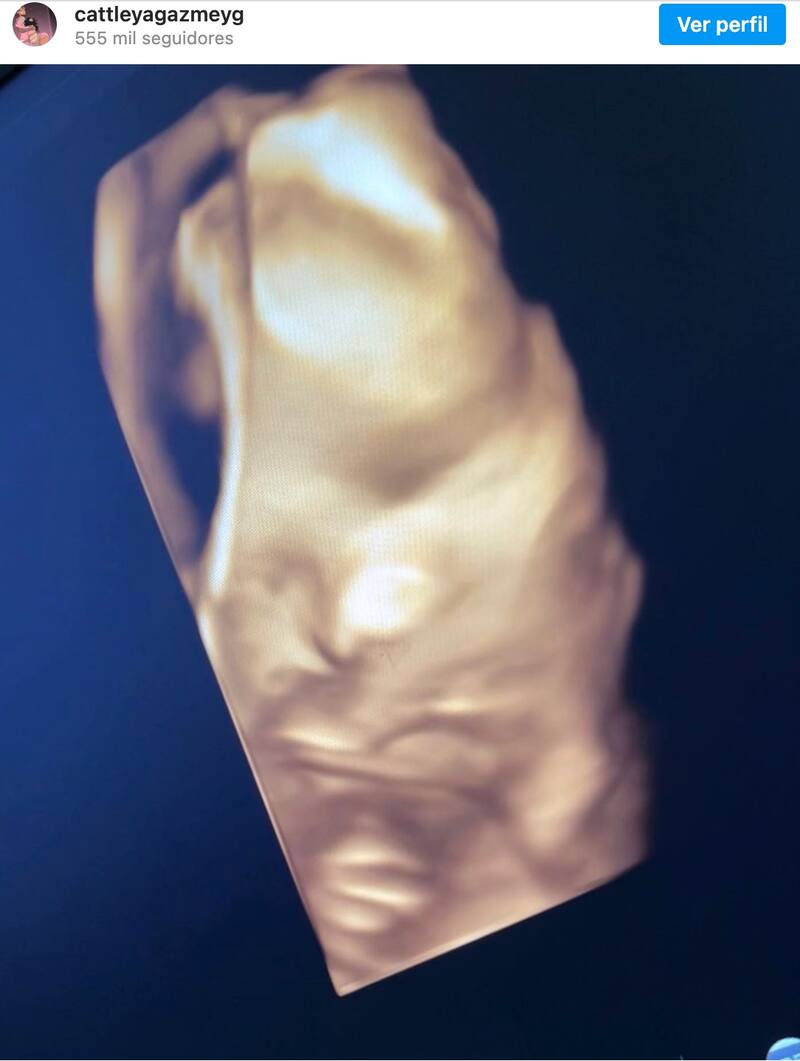

La esposa de Anuel AA compartió en el perfil oficial de su pequeña Cattleya la primera foto de su rostro después de acudir al doctor en un ultrasonido 3D. Yailin demostró que está en una de las etapas más bonitas de su vida y que está disfrutando al máximo del crecimiento de su primer bebé.

“Flor hermosa, flor divina, a quién se parece Cattleya?”, escribió en la plataforma de Instagram.